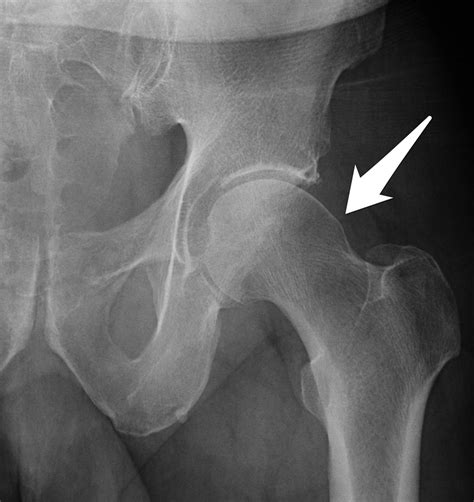

In patients with Cam Impingement, the shape of the femoral head is not perfectly round. Instead, it has an abnormal bony growth, often referred to as a "cam" lesion. Because this bone is irregular, it cannot rotate smoothly within the socket. As you move, especially during hip flexion or internal rotation, this extra bone bumps into the rim of the socket, pinching the labrum and causing damage to the articular cartilage.

If you suspect you have Cam Impingement Hip, a physical examination is the first step. An orthopedic specialist will perform specific tests, such as the FADIR test (Flexion, Adduction, Internal Rotation), which is designed to reproduce the impingement and pain. Following this, imaging is usually required to confirm the diagnosis.

• X-rays: Standard views help the doctor visualize the shape of the femur and the degree of the bony prominence.

If physical therapy and activity modification fail to provide relief after several months, surgical options may be discussed. Hip arthroscopy is a minimally invasive procedure where the surgeon uses small incisions to remove the excess bone (the “cam” lesion) and repair any torn labral tissue. This “reshaping” of the hip anatomy aims to restore normal movement patterns.